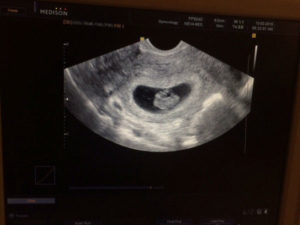

- УЗИ, определяет 8 недель беременности размер плода, состояние кровоснабжения, плаценты и т.д.;

8 недель беременности размер плода составляет примерно 2 сантиметра, а вес около 6 грамм. Это приблизительно размер клубники.